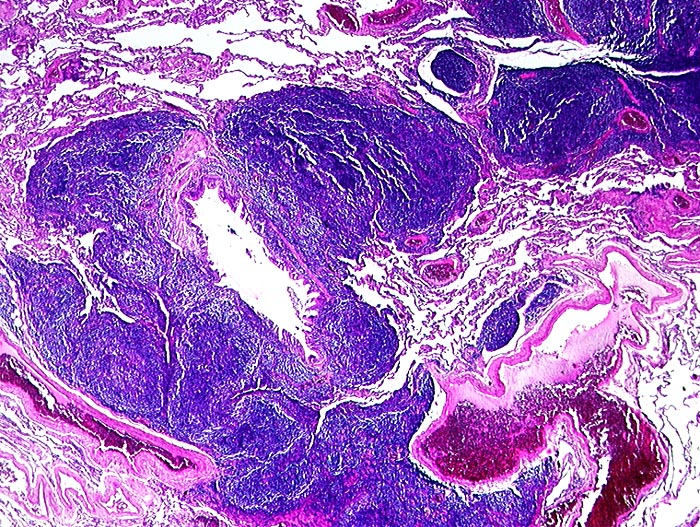

Marginalzonenlymphom: extranodal vom MALT Typ

Lunge

Dichtes Lymphominfiltrat entlang der Lymphspalten um einen Bronchiolus.

Hier: Kleinerer Herd hilusnah entlang Lymphgefässspalten (makroskopisch wie Lymphangiosis carcinomatosa imponierend). Grösserer Herd subpleural 2.4cm Durchmesser. Hiluslymphknoten nicht befallen. Stadium IE.

Verdacht auf peripheres Lungenkarzinom. Peripherer Rundherd als einzige Tumormanifestation im CT.

Altersgipfel pulmonaler MALT Lymphome 6.-7. Dekade. Meist solitärer Rundherd, weniger häufig multinodulärer Befall und Pleuraerguss. Bei der Mehrzahl Stadium IE initial. Sehr indolenter Verlauf mit günstigster Prognose aller extranodalen Marginalzonen Lymphome.